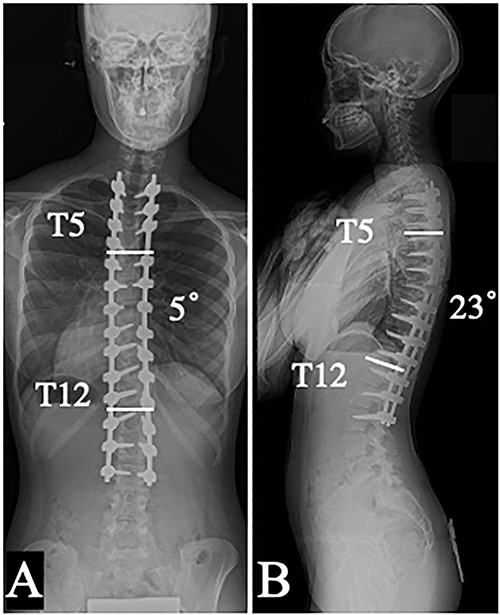

A 13-year-old girl was diagnosed with AIS classified as Lenke type 1A- since her standing radiographs demonstrated the main thoracic (MT) curve of 62° from T6 to L2, the thoracic kyphosis (TK) angle of 7° (Figs 1A and 2A). Posterior corrective surgery was performed at the T5-L2 level to prevent the progression of deformity. The MT curve was corrected to 17°, indicating a correction rate of 72.6%. The TK improved to 27° and acquired physiological kyphosis. At the 1-year follow-up, both the coronal and sagittal alignments were maintained, and the patient restarted sports activities without any impairment (Figs 1B and 2B). However, the patient returned to our hospital complaining of wound swelling 1 month later. Laboratory data showed a mild inflammatory reaction, but magnetic resonance imaging showed subcutaneous fluid accumulation, and its culture revealed Methicillin-susceptible Staphylococcus aureus. Although the infection subsided with debridement surgery and antibiotics, it recurred 3 months later. Inevitably, implant removal surgery was performed after confirming bony fusion by computed tomography (CT) scan. Following this, there was almost no loss of the coronal alignment; however, the sagittal alignment progressively deteriorated (Figs 1B, C). Even though hard bracing was introduced to prevent the progression of kyphotic change, the TK progressed to 74° in a year (Fig. 2C). As a result, the height of the patient decreased by 2.5 cm. The patient complained of back pain in the supine position and the radiograph revealed rigid thoracic hyper-kyphosis that was not corrected by fulcrum bending (Fig. 2D). Therefore, revision surgery was performed 15 months after implant removal. Solid bony fusion was confirmed from T5 to L2. However, slight intraspinal mobility was observed at T7/8 and T10/11, even though the preoperative CT scan showed no clear evidence of pseudarthrosis (Fig. 3A). Pedicle screws were placed from T2 to L3 using an O-arm navigation system due to the significant changes in anatomical structure. Schwab Grade 2 osteotomies were performed again with the removal of fusion masses at multiple levels including at T7/8 and T10/11and the kyphosis was corrected using the cantilever technique (Fig. 3B). At the 14 month follow-up, there was no evidence of recurrence or residual infection, and the MT and TK were corrected and maintained at 5° and 23°, respectively (Figs 4A, B).

Coronal (A) and sagittal (B) plain radiographs in a standing position taken 14 months after the revision surgery.